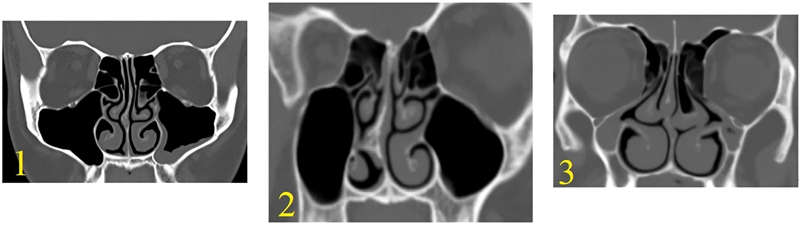

Introduction  The preoperative assessment of the computed tomography (CT) characteristics of the maxillary sinus helps to preserve its anatomical and functional integrity during and after surgery. Objective  To use CT scanning to identify maxillary sinus variations and types that were not previously published. Methods  The present study was carried out on 110 paranasal CT scans (220 sides). Axial images were obtained with multiplanar scans, to visualize details in coronal and sagittal planes for all subjects. Results  Among the 110 CTs (220 sides) of the maxillary sinus's floor, there were 53.2% type 1, 29.1% type 2, 10% type 3, and 7.7% type 4, with significant difference between genders. The most common maxillary sinus floor was type 1. The lateral maxillary sinus wall was found to be type 1 in 32.7%, type 2 in 65%, and type 3 in 2.3%, with a significant difference between genders. The most common lateral wall of the maxillary sinus type was type 2. The orbital floor was found to be type 1 in 0.9%, type 2 in 21.3%, type 3 in 50.5%, and type 4 in 27.3%, without significant difference between genders. Asymmetry was detected between the right and left sides for the maxillary sinus floor of in 22.7%, lateral maxillary wall in 16%, and orbital floor (maxillary roof) in 30%. Conclusion  This study aims to increase surgeons' awareness of maxillary sinus variations, creating new classifications for usage and communication in the otorhinolaryngology and endoscopic fields. It could also be helpful for training medical residents.

Abstract Image